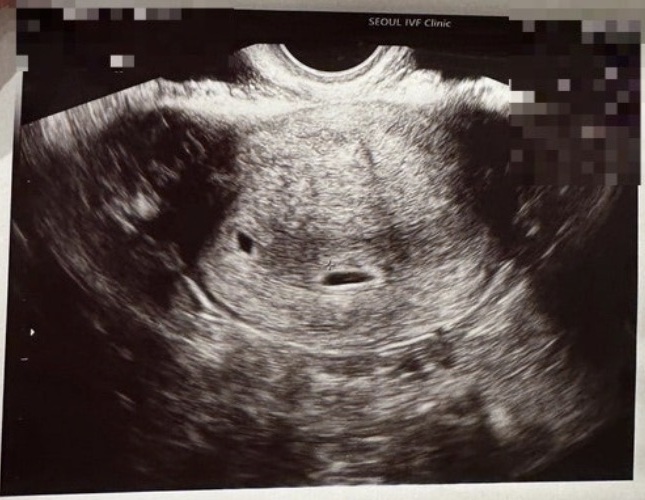

| 가슴 떨리는 임신 이야기를 공유해 주세요. | 시험관 시술을 준비하며 걱정과 두려움이 많이 앞섰습니다. 과정 하나하나가 쉽지는 않았지만 선생님들의 설명이 큰 도움이 되었고, 작은 수치 하나에도 함께 설명해 주셔서 점점 신뢰가 생겼습니다. 시술 후 두 줄이 선명하게 나타났을 때는 기쁨보다도 믿기지 않는 마음이 더 커서 한참을 바라보게 되었고, 심장소리를 처음 들었을 때는 숨을 쉬는 것조차 조심스러울 만큼 벅찼습니다. |

| 치료 도중 느꼈던 가장 기뻤던 순간과 절망적인 것들은 무엇인가요? 잊지 못할 경험이 있나요? | 가장 기뻤던 순간은 두 줄을 확인했을 때와 피검사 수치를 통해 임신을 확인하고, 초음파로 아기를 눈으로 보았을 때였습니다. 반면, 태아 하나가 도태되었을 때는 마음이 무너질 만큼 힘든 순간이었습니다. |